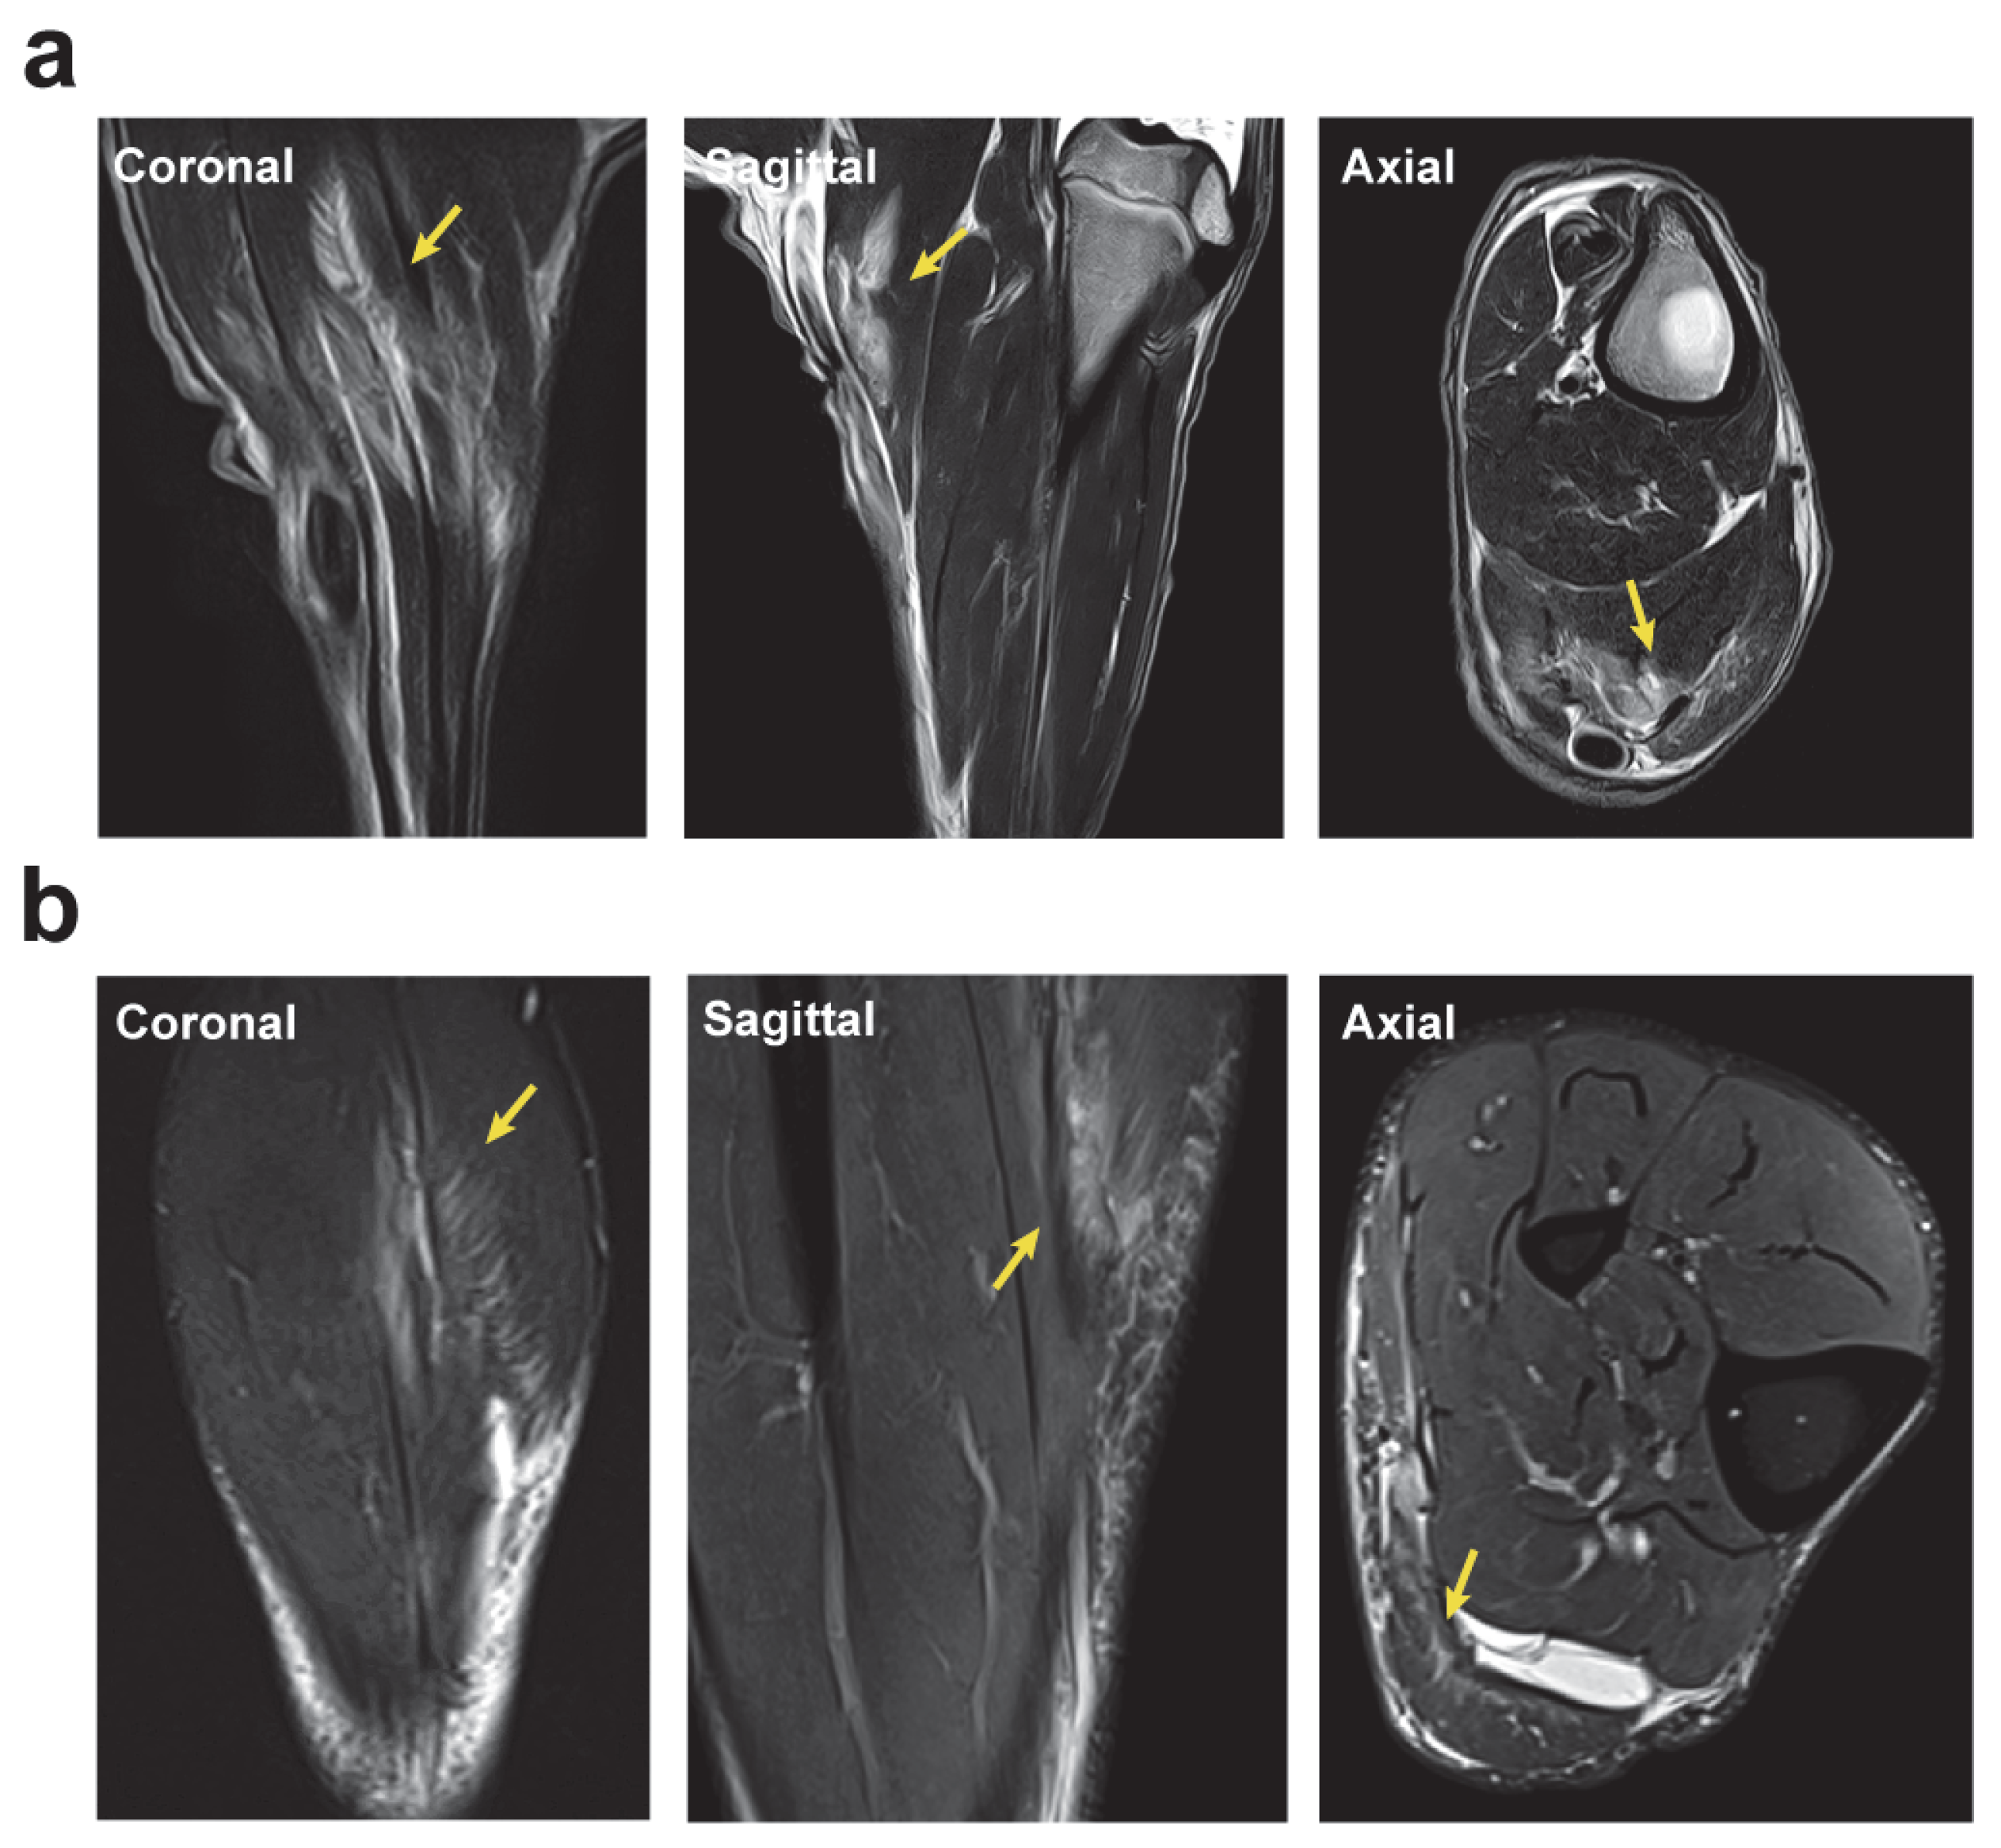

2.4. Magnetic Resonance Imaging Analysis of the Longitudinal Evolution of Skeletal Muscle Injury

2.5. Surgically Induced Skeletal Muscle Injury in a Sheep Model Mimics Muscle Lesions Observed in Human Athletes